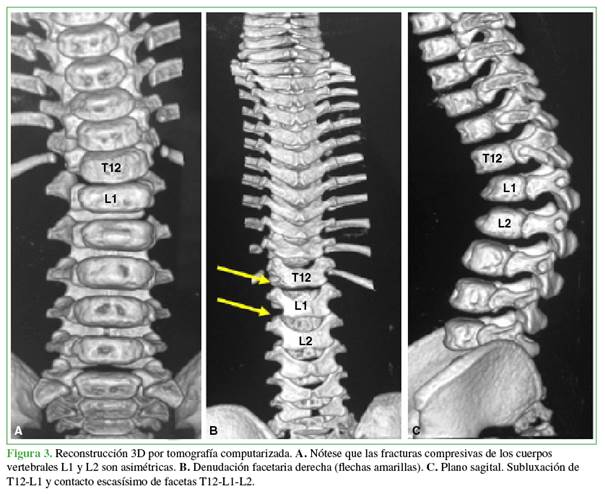

La resonancia magnética no aportó datos de interés y la tomografía computarizada fue indispensable para comprobar una denudación facetaria de T12-L1-L2 izquierda y para detallar los aspectos anatómicos de los pedículos (Figura 3).